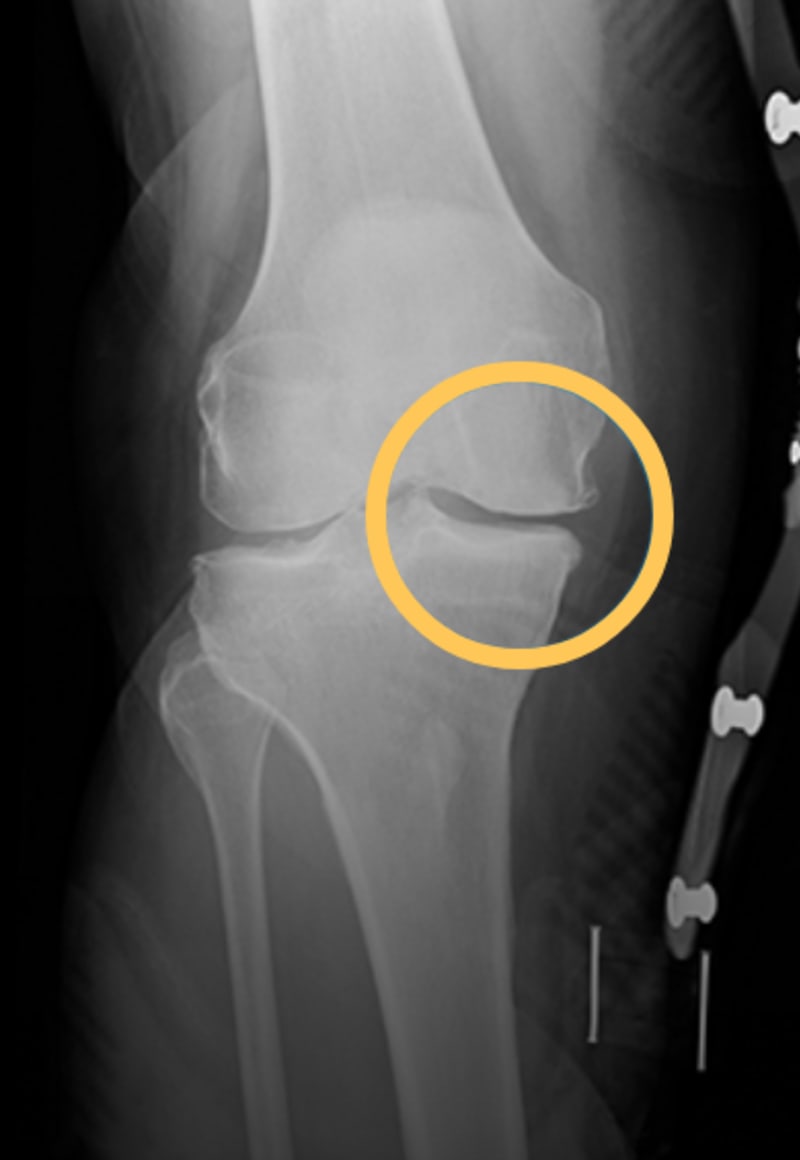

Knee OA without bracing

(bone-on-bone contact)